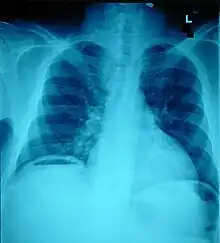

Ten percent of people with polytrauma who had no signs of abdominal injury did have evidence of such injuries using radiological imaging.[1] Diagnostic techniques used include CT scanning, ultrasound,[1] and X-ray.[7] X-ray can help determine the path of a penetrating object and locate any foreign matter left in the wound, but may not be helpful in blunt trauma.[7] Diagnostic laparoscopy or exploratory laparotomy may also be performed if other diagnostic methods do not yield conclusive results.[5]

The small intestine takes up a large part of the abdomen and is likely to be damaged in penetrating injury.[5] The bowel may be perforated.[4] Gas within the abdominal cavity seen on CT is understood to be a diagnostic sign of bowel perforation; however intra-abdominal air can also be caused by pneumothorax (air in the pleural cavity outside the lungs that has escaped from the respiratory system) or pneumomediastinum (air in the mediastinum, the center of the chest cavity).[4] The injury may not be detected on CT.[4] Bowel injury may be associated with complications such as infection, abscess, bowel obstruction, and the formation of a fistula.[4] Bowel perforation requires surgery.[4]